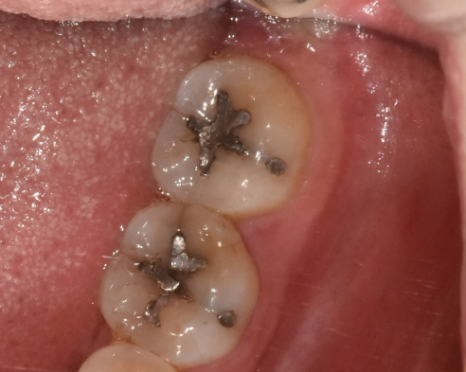

- 이제는 역사속으로... 아말감

240214

이제는 사용하지 않기에 말씀을 안드리려다

여전히 많은 환자분들 입안에서 볼 수 있는 은니 색깔 이것..!

예전에 강동구 치과에서도 많이 사용했던..

레진 대신에 보험 적용이 가능한 아말감 치료

똑같이 치아 땜질 치료이지만

떼운 주변으로 벌어져 충치가 또 생기거나

수은이 나와 몸에 유해해요~

그래서 이제는 잘 사용하지 않는데요.

환자분들께서 예전 기억으로 가끔 찾으셔서

준비해보았습니다.